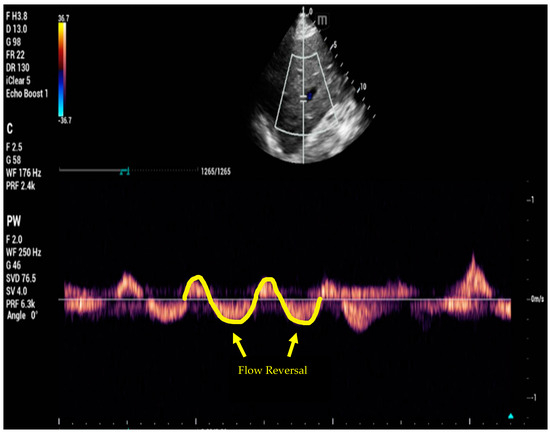

6. Venous Excess Ultrasound Score

- Beaubien-Souligny, W.; Rola, P.; Haycock, K.; Bouchard, J.; Lamarche, Y.; Spiegel, R.; Denault, A.Y. Quantifying systemic congestion with Point-Of-Care ultrasound: Development of the venous excess ultrasound grading system. Ultrasound J. 2020, 12, 16. [Google Scholar] [CrossRef]

- Spiegel, R.; Teeter, W.; Sullivan, S.; Tupchong, K.; Mohammed, N.; Sutherland, M.; Leibner, E.; Rola, P.; Galvagno, S.M.; Jr Murthi, S.B. The use of venous Doppler to predict adverse kidney events in a general ICU cohort. Crit. Care 2020, 24, 615. [Google Scholar] [CrossRef]

- Andrei, S.; Bahr, P.A.; Nguyen, M.; Bouhemad, B.; Guinot, P.G. Prevalence of systemic venous congestion assessed by Venous Excess Ultrasound Grading System (VExUS) and association with acute kidney injury in a general ICU cohort: A prospective multicentric study. Crit. Care 2023, 27, 224. [Google Scholar] [CrossRef]

- Argaiz, E.R.; Rola, P.; Gamba, G. Dynamic Changes in Portal Vein Flow during Decongestion in Patients with Heart Failure and Cardio-Renal Syndrome: A POCUS Case Series. Cardiorenal Med. 2021, 11, 59–66. [Google Scholar] [CrossRef]

- Rola, P.; Miralles-Aguiar, F.; Argaiz, E.; Beaubien-Souligny, W.; Haycock, K.; Karimov, T.; Dinh, V.A.; Spiegel, R. Clinical applications of the venous excess ultrasound (VExUS) score: Conceptual review and case series. Ultrasound J. 2021, 13, 32. [Google Scholar] [CrossRef] [PubMed]